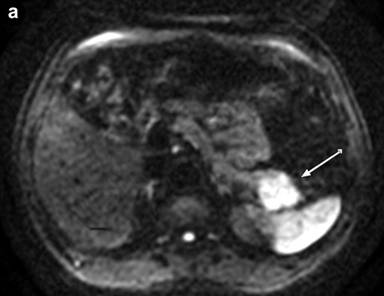

Medical image diagnosis by radiologists is based on their training, experience and individual judgment to visually identify key image features, which aid them in making decisions. Texture analysis is a wide range of methods incorporating image filtering techniques (wavelets, Gabor, grey level co-occurrence matrix, etc.) that can be used to describe variations in image intensity or patterns. Some of these patterns or differences might be imperceptible to the naked eye but texture analysis with statistical pattern recognition techniques can be used to evaluate texture pattern differences in images. A basic routinely used feature, for example, is size. Texture feature analysis of CT images has shown promise in pancreatic cancer [14]. Similarly, work has been done to identify features on FDG-PET images in other tumors, such as esophageal, [15]. Tuli et al. [7] found texture features of the FDG-PET images in a small sample of subjects that correlated with response to SBRT. By using this pilot data and incorporating knowledge gained from work in esophageal cancer, a prospective study would be helpful for further assessment. In addition, some centers routinely use MRI (Figure 1) for staging of pancreatic adenocarcinoma. Feature analysis of MRI images may hold more information [16]. Since gemcitabine interferes with DNA synthesis, MRI techniques like diffusion weighted imaging may be helpful since diffusion weighted imaging is affected by changes in cellular density.

|

Figure 1. A 76-year male with poorly differentiated ductal adenocarcinoma in the tail with perineural invasion and lymphovascular invasion on the resection specimen Total of 4/15 positive lymph nodes were found. Genetic testing was negative for EGFR, KRAS, and BRAF mutations. MRI before surgery shows: a. restricted diffusion on diffusion weighted imaging; b. little to no enhancement two minutes post-contrast injection. c. Follow-up FDG-PET-CT two months later showed multiple metastases in the liver with SUV up to 9.8. |